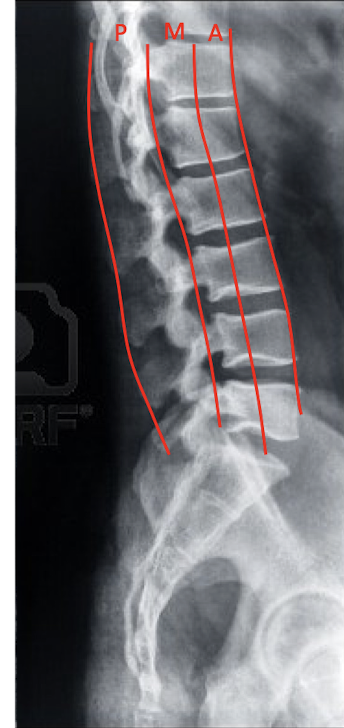

Define the 3 Column Concept:

Anterior Column

Middle Column

Posterior Column

3 Column Concept:

What structures are included in:

Anterior Column:

2

Middle Column:

2

Posterior Column:

4

Anterior Column

Anterior Longitudinal Ligament

Ant. 2/3 of Vertebral Body

Middle Column

Posterior 1/3 of the Vertebrae

Posterior Longitudinal Ligament

Posterior Column

Posterior Ligament Complex

Vertebral Arch

Facets

Ligamentum Flavum